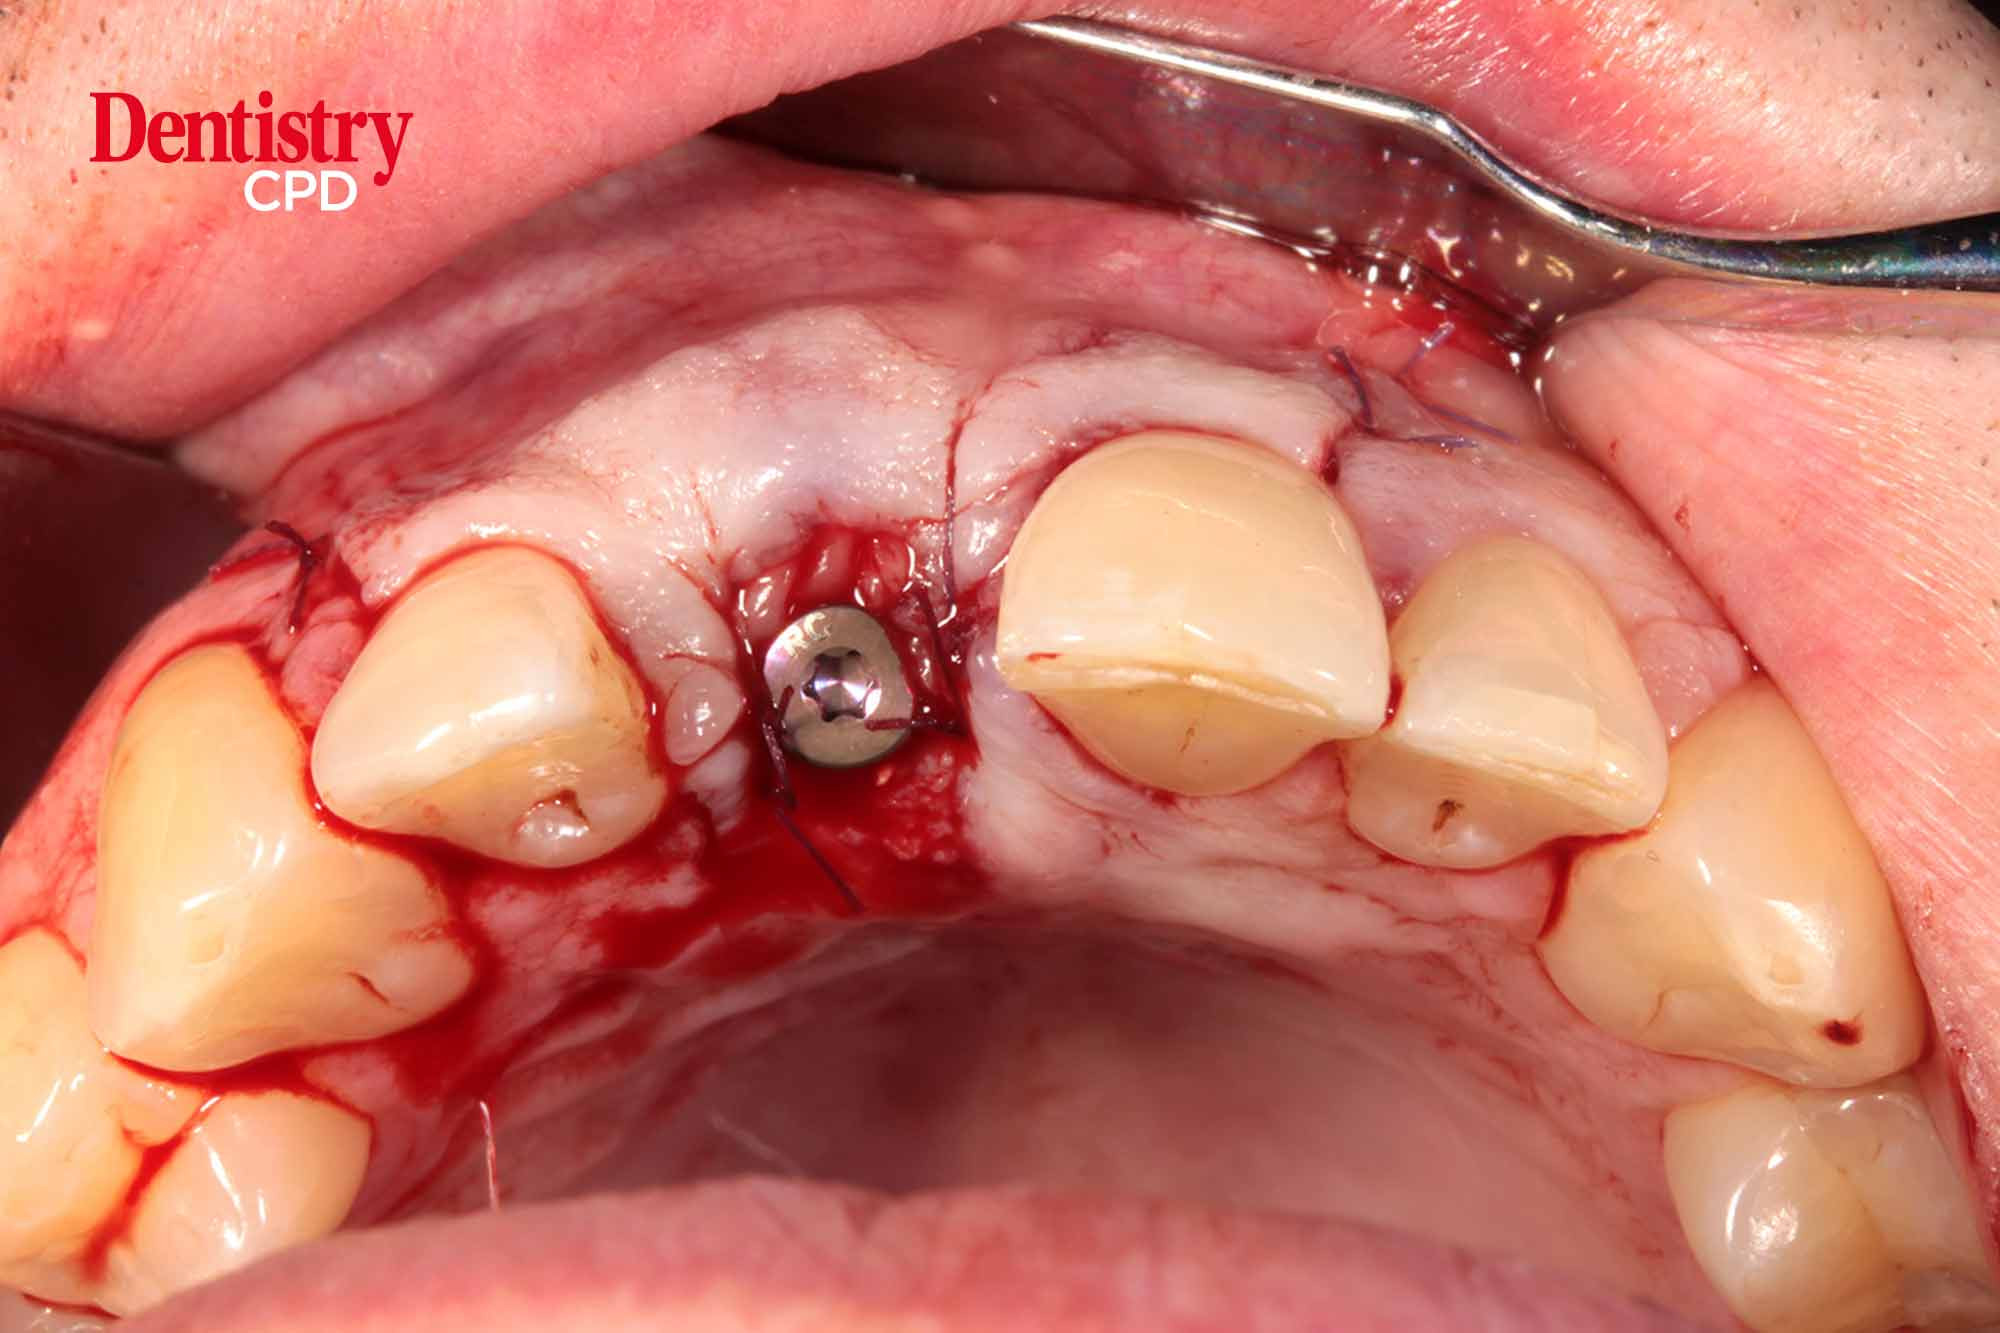

Immediate implant placement

Nilesh Parmar examines how immediate implant placement can help skilled clinicians keep up with patient demands

To explore immediate implant placement, its advantages and disadvantages and the factors influencing case selection.